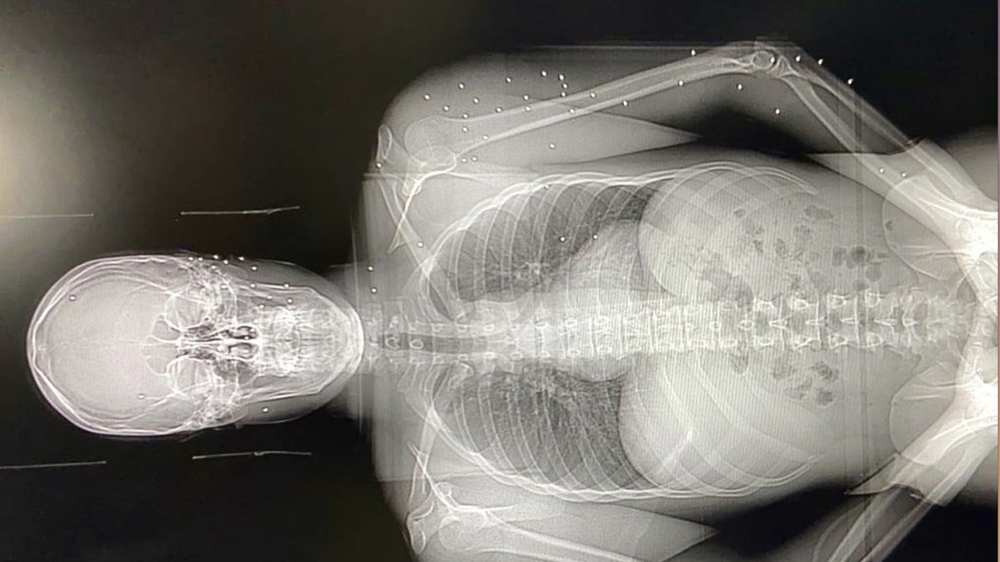

At least 728 people were injured during Saturday’s protest, including many receiving wounds to head, neck and chest. Wounds were consistent with both rubber bullets and birdshot.

Two doctors who treated protesters wounded with birdshot told Al Jazeera they had seen wounds consistent with both close-range and long-distance fire.

Fred Bteich, a surgeon at Beirut’s Hotel Dieu Hospital, said one man was shot from a maximum distance of 15 metres (49 feet). He said one of the pellets entered the right side of the 33-year-old man’s heart, missing a major artery by 1cm (0.4 inches).

Due to the sensitive location of the pellet, surgeons were unable to remove it from the man’s heart. This has the potential to cause complications in the future, Bteich said.

The same man was also hit by a rubber bullet fired at close range, which logged inside his body and had to be surgically removed.

Chaktoura said those treated included a 22-year-old man and a 55-year-old woman. The first had several pellets lodged in his body, with one piercing his spleen, kidney and lodging near his back. His condition was stable.

The woman, however, was shot in the stomach and pancreas and was in unstable condition, requiring emergency surgery.

One patient was brought in with at least 50 pellets spread across his body.

Chakhtoura also noted a number of people had come in with more superficial wounds, consistent with birdshot fired from a farther distance away.